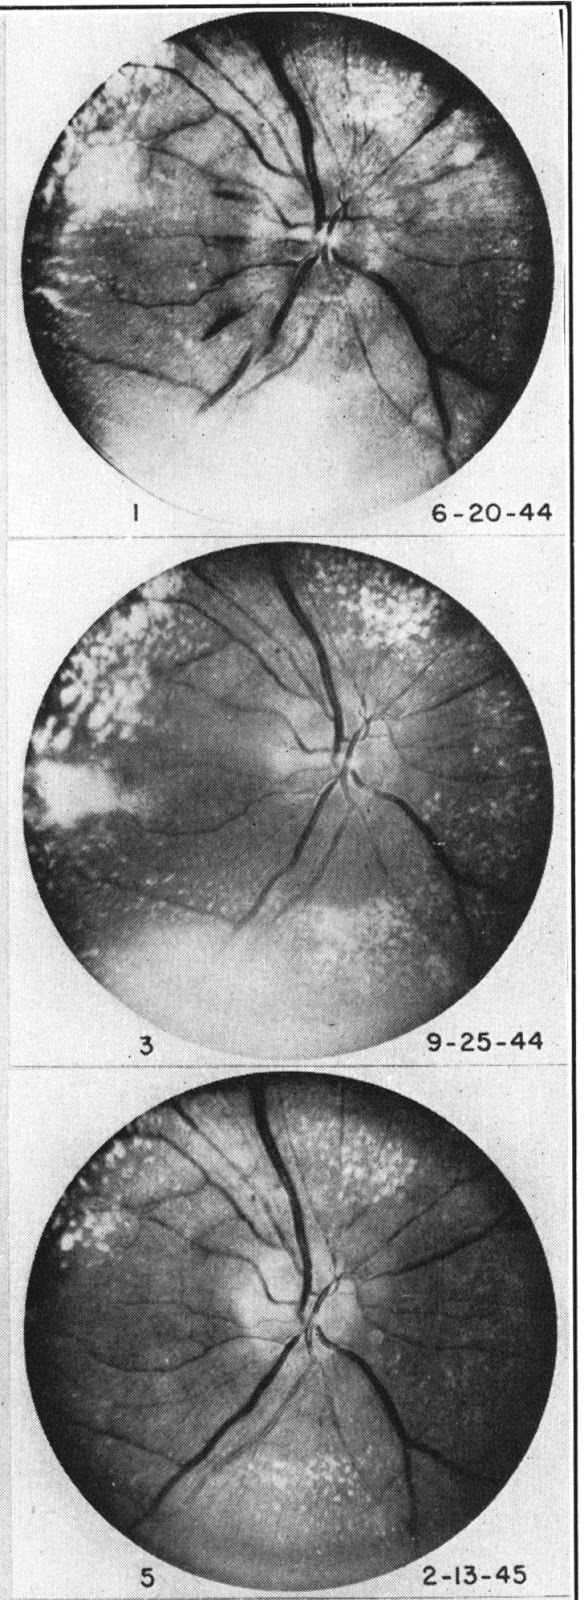

Robust and practical sphygmomanometers (mercury and aneroid) became available in the early 1900s, but regular recording of blood pressure did not become widely routine until the 1920s and 30s. Until then, palpating the pulse offered the only insight, except that ophthalmoscopy could show severe hypertensive retinal changes, neuro-retinitis albuminurica (Figure). The ophthalmoscope had been invented in 1851, but only had electric bulbs after 1900.

| From Kempner 1946 Courtesy of the New York Academy of Medicine Library |

Low salt diets had been tested with some success in Paris in 1904, but Kempner’s 1944 Rice and Fruit Diet was widely influential. It included 2,000-2,400 calories from mostly carbohydrate; just 25g of protein, 5g of fat, and only 0.35g of salt. If adhered to, it was often able to lower blood pressure, especially in patients with kidney disease. However patients found it dull, tasteless, and hard to stick to. Others observed that the extremely low salt content was critical, but made adherence difficult.

Figure 1 shows improvements in the appearance of the retina over 8 months in a patient on Kempner’s rice and fruit diet (Kempner 1946). Courtesy of The New York Academy of Medicine Library.